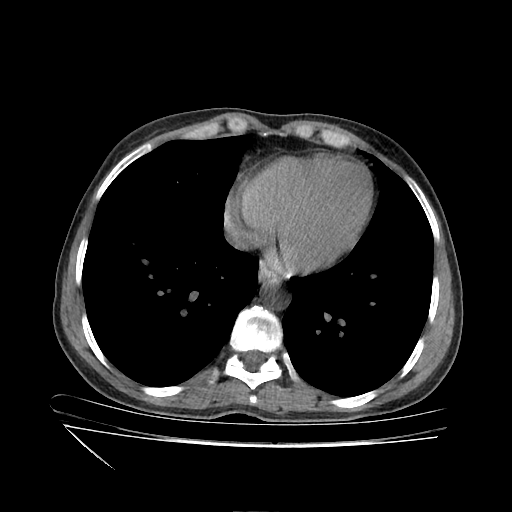

Original VENOUS CT scan

Full window (WL 1023.5, WW 4095 β†’ Low βˆ’1024, High +3071)

Actual HU range: [-160.0, 240.0]

Lung window (WL -600, WW 1500 β†’ Low βˆ’1350, High +150)

Actual HU range: [-160.0, 150.0]

Mediastinum window (WL 40, WW 400 β†’ Low βˆ’160, High +240)